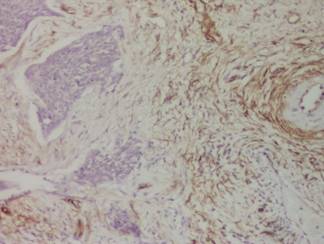

Figura 7: Carcinom invaziv. Importanta neogeneza vasculara în

interstitiul placardelor tumorale. Imunoreactie pentru CD 3l, x 40

Nu s-a evidentiat o corelatie semnificativa statistic între microdensitatea vasculara MVD, nediferentiat pe criteriul tipului de vas (mature, intermediare, imature), si stadiul de boala pentru pacientele stadializate CIS, CMI si CI.

Figura 8: Corelarea tipului de vase cu stadiul bolii

Comparând valorile medii MVD, nediferentiate pe tipuri de vase pentru cele trei stadii analizate: CIS, CMI si CI, s-au constatat diferente mici ale acestora. Aceste valori nu au indicat criterii de departajare evidente pentru cele trei stadii de boala, mai ales pentru stadiile CIS si CMI, pentru care diferenta a fost si mai mica, respectiv de o unitate. Nu s-au constatat diferente semnificative între limitele maxime ale numarului de vase/câmp în raport cu stadializarea, indicând astfel particularitatile genetice deosebite ale fiecarui pacient.